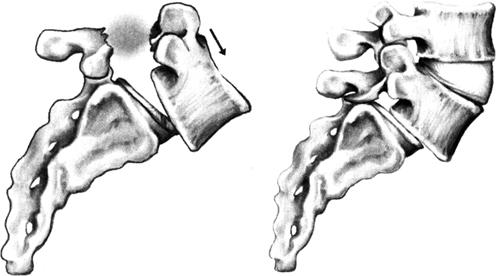

颈椎的关节面向上,约成45°倾斜,C2~C3之间的倾斜度常有变化。关节囊较为松弛,外伤时容易引起半脱位。颈椎椎间关节构成椎间孔的后壁,前与颈神经根与椎动脉邻近。上腰椎的椎间关节面近似矢状位,腰骶部则近似冠状位。椎间关节囊较松弛,借薄弱的纤维束加强。在下腰部,有坚强纤维性结构与椎弓板相连,并部分为棘间韧带所代替,前部为黄韧带。

椎间关节构成椎间管的后界。不同平面腰椎间盘的后面与关节突的关系有差异。在下腰部,特别是L5~S1,或有时在L4~L5,当直立时,椎间盘的后面与下一脊椎骨的上关节突前面相对,这部分椎间盘正常位于椎间管的下部。